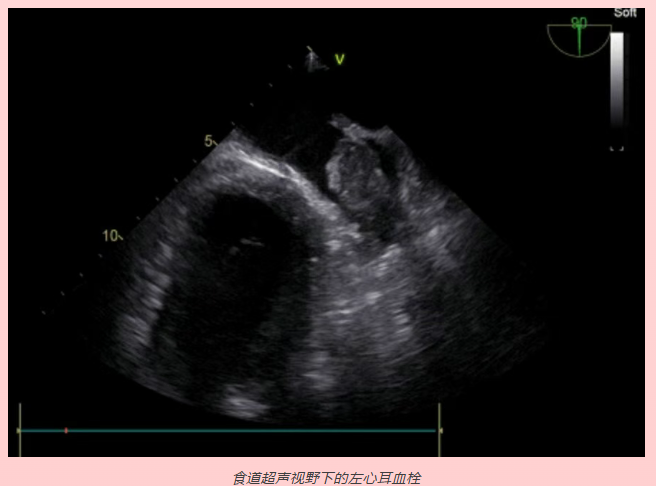

王阿姨,女性,59岁,因心悸不适3年,再次发作3天来我院就诊。门诊检查心电图提示:心房颤动,遂收治入院。完善相关检查后,心内科徐闽医生与患者协商,拟行“房颤射频消融术”。心内科徐医生告诉患者:“手术前还需要再完善一个检查---经食道心脏超声检查,了解一下您心脏内部有没有血栓,因为房颤时,血液容易在心脏内淤滞、沉积而产生血栓,当血栓脱落后,随着血液流动可导致多器官栓塞,出现如头痛、心绞痛、腹痛、腰痛等危险的并发症;而我们则需要经食道心脏超声检查来明确您心脏内有无血栓,在确保安全的前提下才可以给您做射频消融手术”。患者经过食道彩超检查没有发现血栓后,心内科医生给患者成功进行了射频消融,王阿姨说我的心再也不乱跳了,术后随访复查原先明显增大的心脏恢复了正常。

2.左心耳和左房的血栓,尤其是左心耳的血栓,房颤患者做射频消融术前做经食管超声心动图了解左心房及左心耳是否有血栓形成,可以减少手术并发症。